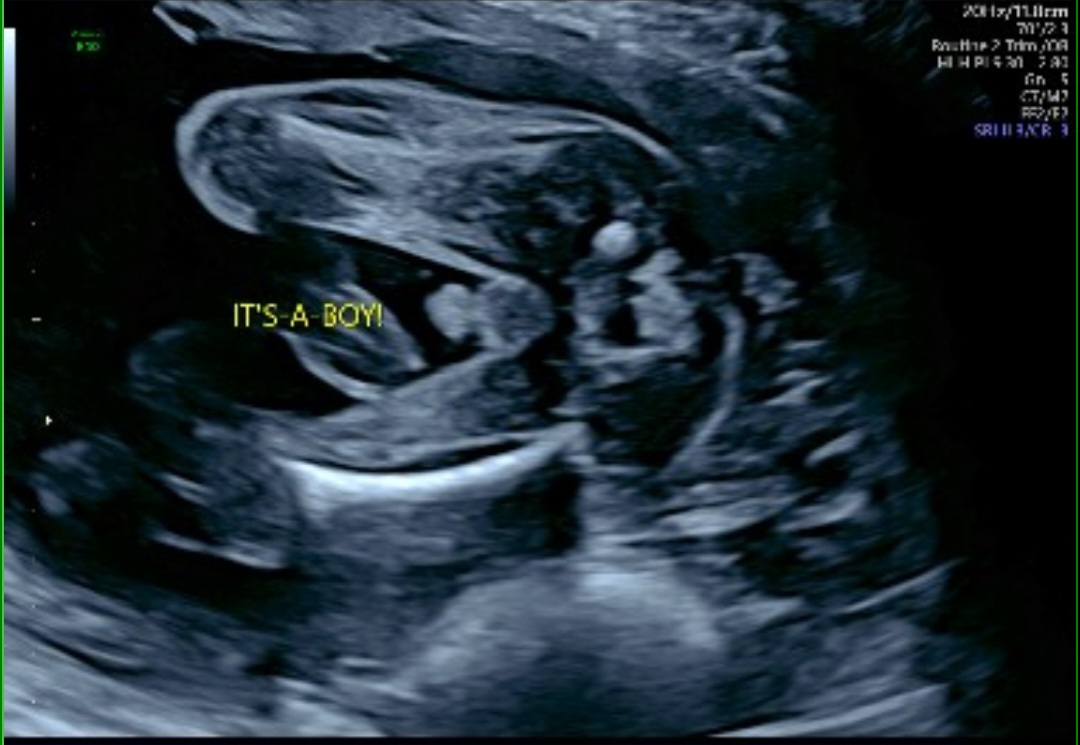

So excited to welcome our little boy to the world!! We knew it was gonna be a boy from day one 💕💕 so happy we were right and hes doing good!!

Report